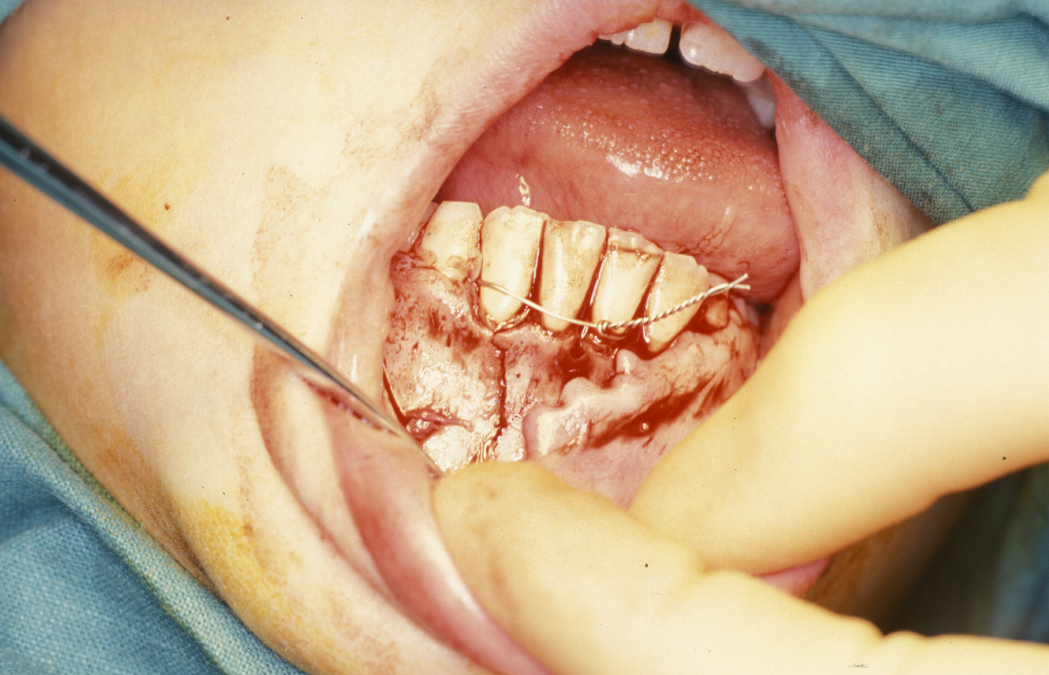

Definitive surgery usually involves open reduction and internal fixation (ORIF) under general anaesthesia, ideally using nasoendotracheal intubation. This allows the patient’s mouth to be closed and the teeth to be manipulated into their normal occlusion. This manipulation helps reduce the mandible into the prefracture bone position. Temporary intermaxillary fixation (IMF) is applied using a variety of techniques (trainee’s hand, eyelets, transalveolar screws (see Figure 1 and Figure 2), ‘rapid IMF’, arch bars). This helps to hold the fracture in its reduced position. Placing a bridle wire or tension band around the teeth can help reduce and temporarily fix the fracture.

Under direct vision via buccal sulcus incisions (incision in the depression between cheek and arch of jaw) the mandibular fracture is exposed and reduction confirmed (see Figure 3).